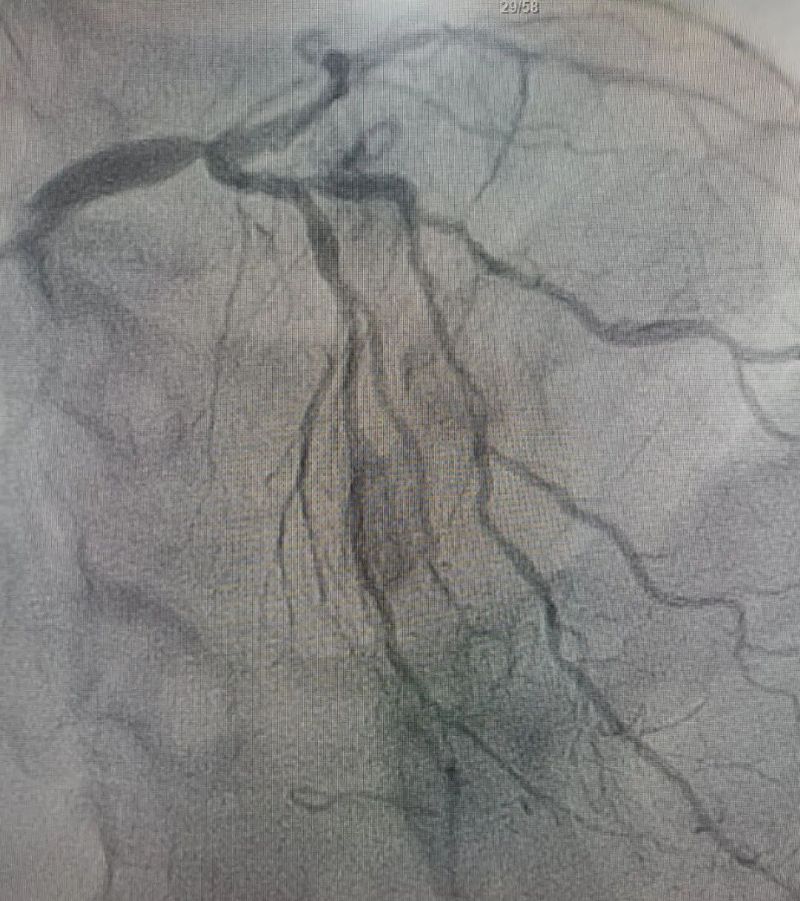

術(shù)中造影顯示,左主干至前降支近段重度狹窄——這正是導(dǎo)致心臟缺血、誘發(fā)室顫的“罪魁禍?zhǔn)住?。主動脈球囊反搏植入、球囊擴張、支架植入......介入團(tuán)隊精準(zhǔn)操作,一氣呵成。堵塞的血管順利開通,血流重新涌動,這顆一度瀕臨停跳的心臟終于重獲生機。

冠狀動脈造影圖

術(shù)前 (左主干至前降支近段重度狹窄)